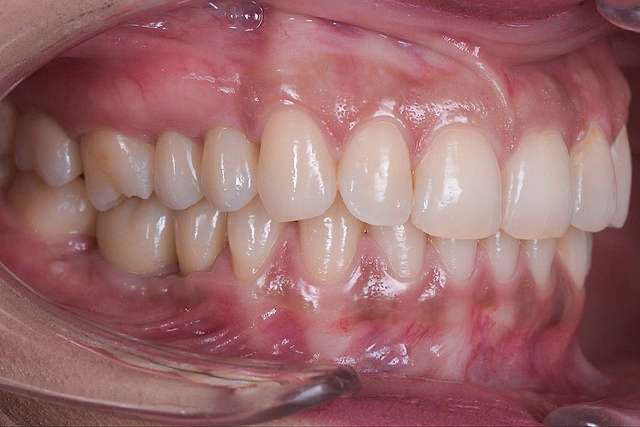

Reducere semnificativa a traumei

Cand procedura insertiei implanturilor dentare se realizeaza cu ajutorul chirurgiei ghidate, chirurgia in sine este mai simpla, iar trauma este mai redusa, in special asupra tesuturilor moi. Astfel, obtinem o vindecare mai rapida, si un comfort sporit post operator.